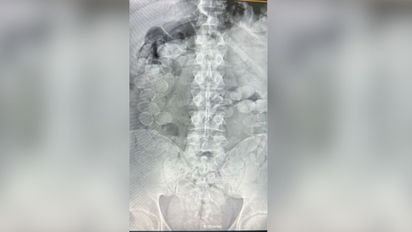

Los sospechosos iban en un colectivo de pasajeros rumbo a Buenos Aires y manifestaron descompostura, por lo que fueron trasladados a un hospital donde se les realizaron placas que mostraron cápsulas de cocaína en su organismo. Uno de ellos está condenado en Brasil por una causa similar.

En un operativo sobre la Ruta Nacional 34 a la altura de Ceres, la Gendarmería Nacional Argentina (GNA) detuvo a dos personas con más de 160 cápsulas de cocaína dentro de su organismo. Los detenidos son de nacionalidad boliviana y venían en un colectivo de pasajeros desde Jujuy.